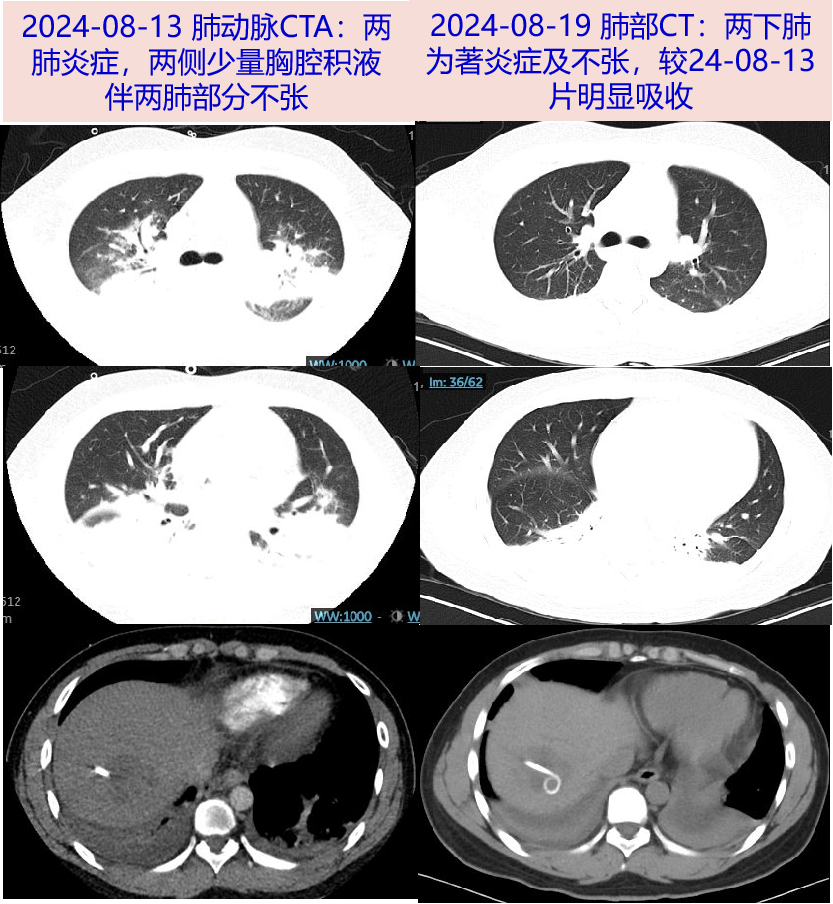

• 肺动脉CTA(08-13 ):两下肺动脉分支远端充盈欠均;两肺炎症,两侧少量胸腔积液伴两肺部分不张。

病史特点:青年男性,既往无慢性疾病基础,急性病程,发热伴恶心呕吐、头晕头痛1周余,WBC、CRP、PCT明显升高,入院前8月9日胸部CT及8月10日腹部CT:未见活动性病灶,腹部增强CT见肝脓肿,介入超声下肝脓肿穿刺引流出血性脓液,肝脓肿临床诊断明确,需进一步明确病原学诊断,继续抗感染治疗。追问病史,08-10夜间出现的呕吐较剧烈,为胃内容物,量较多,约500ml,伴呛咳,考虑呕吐后有误吸,出现明显低氧血症,8月13日肺动脉CTA发现,两下肺动脉分支远端充盈欠均、两肺炎症、两侧少量胸腔积液伴两肺部分不张,肺部病变的原因,考虑如下:

2. 吸入性肺炎:该患者病程中出现两次剧烈呕吐,量较大约500ml胃内容物,伴有明显呛咳,提示可能发生了误吸。呕吐物中含有胃液和细菌,吸入后导致化学性肺炎和继发性细菌感染。文献报道,误吸后数小时内可发生明显的低氧血症,影像学可在数小时内显示单侧或双侧肺部浸润影,本例患者快速出现的肺部炎症,病灶以后坠部位明显,甚至出现肺不张,并伴严重低氧血症,符合吸入性肺炎的临床表现和病程规律

3. 肺动脉栓塞:低氧血症迅速加重,肺动脉CTA报告肺动脉充盈欠均,本例两肺炎症病灶需要考虑肺栓塞可能。但CTA显示两下肺动脉系分支远端的充盈欠均,与两肺病症涉及的部位和广泛程度不符合,因此肺栓塞不能合理解释肺部病灶的原因

• 2024-08-19 胸腹CT平扫:两下肺为著炎症及不张,较24-08-13片部分吸收,两侧少量胸水较前略吸收;肝脓肿穿刺引流术后改变。

患者青年男性,既往无慢性疾病基础,本次急性病程,发热伴恶心呕吐、头晕头痛1周余,WBC、CRP、PCT明显升高,入院前胸部CT:未见活动性病灶,腹部增强CT见肝脓肿,介入超声下肝脓肿穿刺引流出血性脓液,肝脓肿临床诊断明确,完善病原学诊断为肺炎克雷伯杆菌感染,但患者呕吐后出现明显低氧血症(I型呼衰),完善肺动脉CTA:两下肺动脉分支远端充盈欠均;两肺炎症,两侧少量胸腔积液伴两肺部分不张。短期内迅速出现的肺炎和低氧血症,痰mNGS提示口腔菌群,综合患者危险因素评估、抗感染治疗反应及肺炎影像学特征变化,考虑剧烈呕吐后误吸导致的吸入性肺炎。